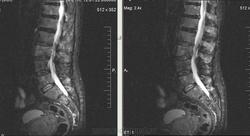

Метастазы рака простаты, кроме измений в позвонках видна сама первичная опухоль и лимфатические узлы (общий и наружный подвздошные слева, ещё один в левой подвздошной ямке).

После добавления томограмм исследования органов малого таза картина стала ещё печальнее...

Да, запустил пациент. До этого были проблемы с мочеиспусканием, рези, болезненность. Лечился самостоятельно от простатита, отмечал временное улучшение.